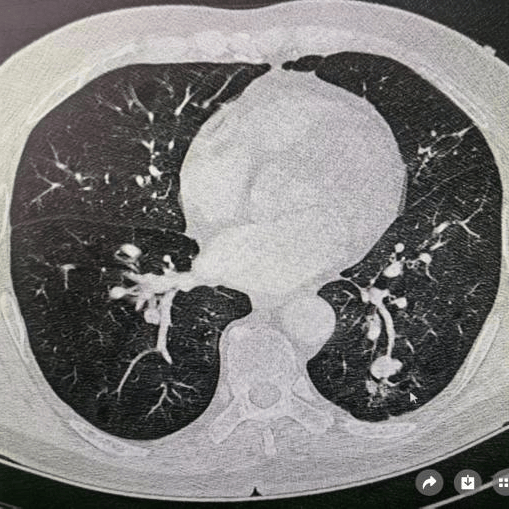

肺结节是指影像学表现为最大径 ≤ 30mm的局灶性、类圆形、较肺实质密度增高的实性或亚实性阴影,可为孤立性或多发性,不伴肺不张、肺门淋巴结肿大和胸腔积液。

多种多样的肺部小结节